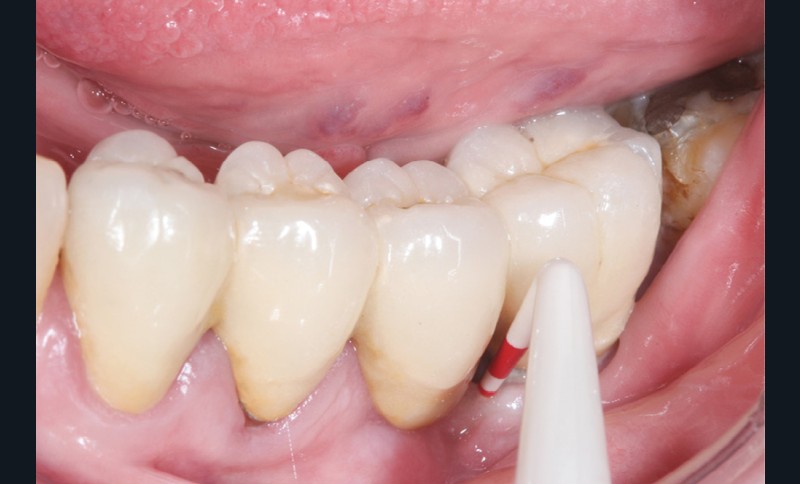

Enfin, la conception prothétique elle-même est à réfléchir, que ce soit en termes de profil d’émergence [18, 19] (pas de surcontour par exemple) (fig. 8) que d’accès à l’hygiène [20, 21] (fig. 9).